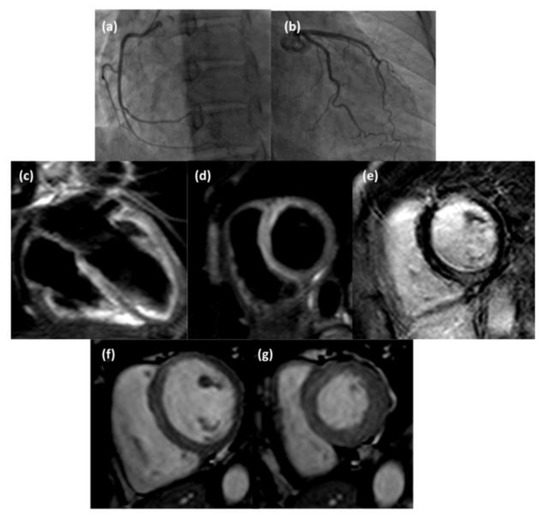

4.1. “Infarct-like” Presentation